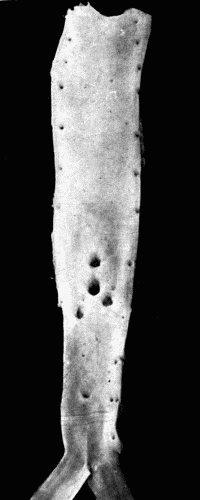

Fig. 3.—Arteriosclerosis of the thoracic and abdominal aorta, showing irregular

nodules, atheromatous plaques, denudation of the intima, thin plates of bone scattered

throughout with spicules extending into the lumen of the vessel. Note the contraction

of the openings of the large branches, the rough appearance of the aorta and the greater

degree of sclerosis of the upper two-thirds, i. e., of the aorta above the diaphragm.

This aorta in the recent state was much thickened and almost inelastic. Fig. 3.—Arteriosclerosis of the thoracic and abdominal aorta, showing irregular nodules, atheromatous plaques, denudation of the intima, thin plates of bone scattered throughout with spicules extending into the lumen of the vessel. Note the contraction of the openings of the large branches, the rough appearance of the aorta and the greater degree of sclerosis of the upper two-thirds, i. e., of the aorta above the diaphragm. This aorta in the recent state was much thickened and almost inelastic.

In the nodular form the lesions are found on the aorta and large branches particularly at or near the orifices of branching vessels. These nodules may increase in size, forming rather large, slightly raised plaques of yellowish-white color. They are, as a rule, irregularly scattered throughout the aorta and branches and tend to be more numerous and larger in the abdominal aorta. The initial lesion is in the media, consisting of an actual dissolution of this coat with rupture of the elastic fibers and infiltration with small round cells. There is thus a weak spot in the artery. Hypertrophy of the intimal cells takes place, layer upon layer being added in an attempt to strengthen the vessel at the injured place. Coincidently with this, there is thickening by a connective tissue growth in the adventitia. The process begins, at least in syphilis, around the terminals of the vasa vasorum. It will be recalled that the blood supply of the inner portion of the media comes[38] from within the vessel itself. As the intimal growth increases, the blood supply is cut off. The inevitable result is softening of the portion farthest from the lumen of the vessel. As a rule there has been a sufficient growth of connective tissue in the media and adventitia to repair the damage done to the media. This softening and dissolution gives rise to a granular debris composed of degenerated cells and fat. This is the so-called atheromatous abscess. There are no leucocytes as in ordinary pus. These "abscesses" are frequent and in rupturing leave open ulcers with smooth bases, the atheromatous ulcer. A further change which often takes place is calcification of the bases of the ulcers and calcification of the softened spots before rupture takes place. This only occurs in advanced cases. (See Fig. 3.)